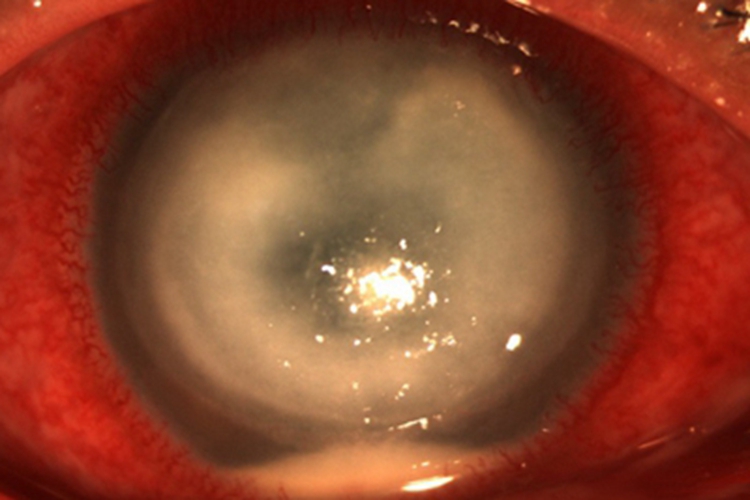

角膜挫伤患者可有明显的眼部疼痛、畏光、流泪及眼睑痉挛等症状,视力也受到影响。上皮缺损区荧光素着色,若发生感染,可出现角膜水肿、增厚以及大小不一的白斑,并引起角膜溃疡。